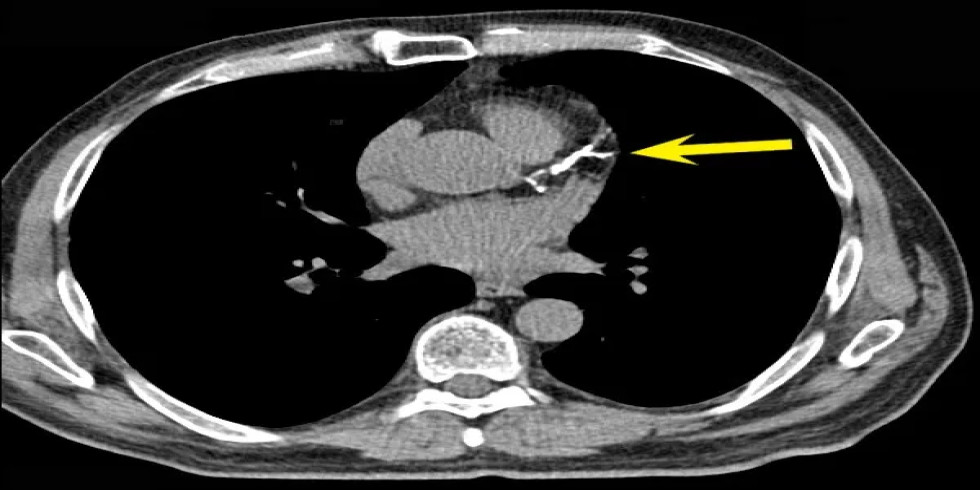

A CT coronary angiogram, also known as CTCA, is a non-invasive imaging test that uses X-rays and a contrast dye to visualize the coronary arteries and detect blockages or other abnormalities. It helps diagnose coronary artery disease by highlighting the arteries and any potential issues within them. Here's a more detailed explanation: What it is: CTCA uses a CT scanner and a contrast dye (usually iodine-based) injected into a vein, typically in the arm, to visualize the coronary arteries. The contrast dye highlights the arteries, making them appear bright on the images produced by the CT scanner, allowing doctors to see the blood flow and identify any blockages or narrowing. How it works: 1. Preparation: Patients may need to avoid eating and drinking for a certain period before the scan and may be given medication to slow their heart rate for clearer images. 2. IV Insertion: An intravenous line (IV) is inserted into a vein, usually in the arm, to administer the contrast dye. 3. Scanning: The patient lies on a table that moves into the CT scanner (a doughnut-shaped machine). The scanner rotates around the patient, taking multiple X-ray images. 4. Image Acquisition: The contrast dye highlights the coronary arteries, allowing doctors to evaluate their structure and identify any blockages, plaque buildup, or other abnormalities. 5. Post-Procedure: Patients can usually resume normal activities immediately after the scan, but may be advised to drink plenty of fluids to help flush out the contrast dye. Purpose: Detect Blockages: CTCA is used to identify blockages or narrowing (stenosis) of the coronary arteries, which can be a sign of coronary artery disease. Assess Plaque Buildup: It can detect the presence and extent of plaque buildup (atherosclerosis) in the arteries, which can restrict blood flow. Evaluate Heart Disease Risk: CTCA helps assess the overall risk of heart disease and can guide treatment decisions. Guide Further Procedures: If significant blockages are found, CTCA can help determine if further procedures like angioplasty or bypass surgery are needed. Potential Risks: Allergic Reaction: A small percentage of patients may experience an allergic reaction to the contrast dye, ranging from mild (itching, hives) to severe (difficulty breathing, anaphylaxis). Kidney Problems: In rare cases, contrast dye can potentially harm the kidneys, especially in patients with pre-existing kidney conditions. Radiation Exposure: CTCA involves exposure to X-ray radiation, but the dose is generally considered low and safe for most patients.